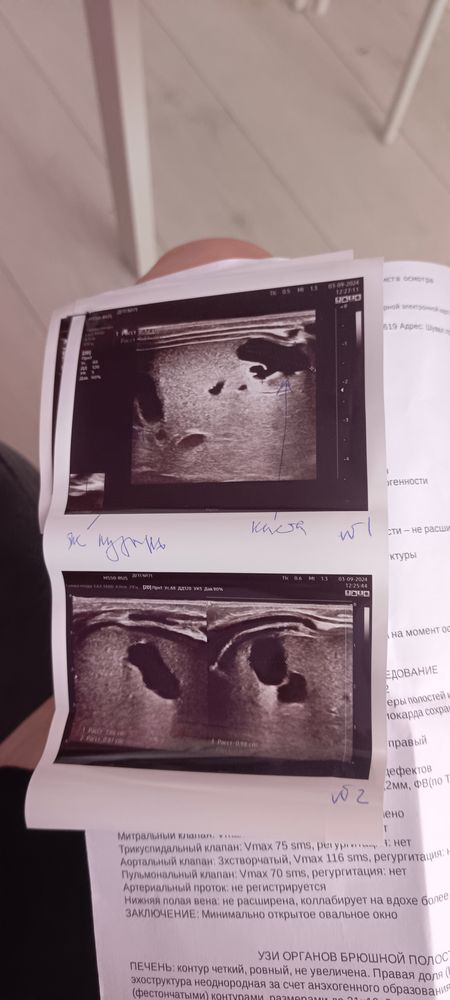

Киста печени у младенца.

Нам 1 месяц, вот проходим медкомиссию. Сходили на узи сказали что у нас киста в печени, что наблюдать будем в динамике, киста в 4м сегменте.